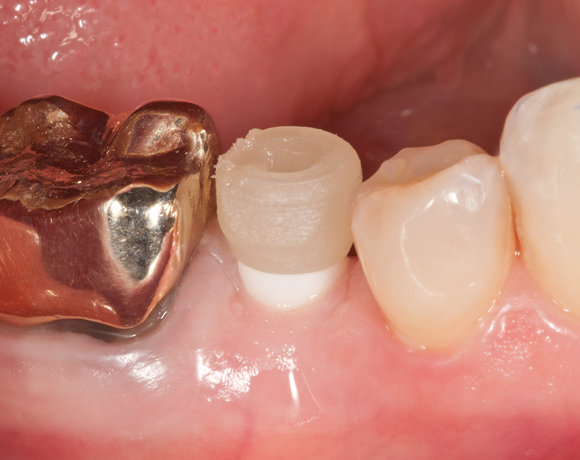

Offene Abdrucknahme bedeutet, dass beim Abformen ein Abdrucklöffel benutzt wird, bei dem über dem Implantat vorab ein loch gebohrt wird, durch das die Schraube des Abdruckpfostens herausragt und nach Aushärten des Abdruckmaterials abgezogen werden kann.

Bei diesem Patientenfall wird die offene Abdrucknahme gezeigt und die Herstellung einer Krone auf einen CAD/CAM Pfosten.